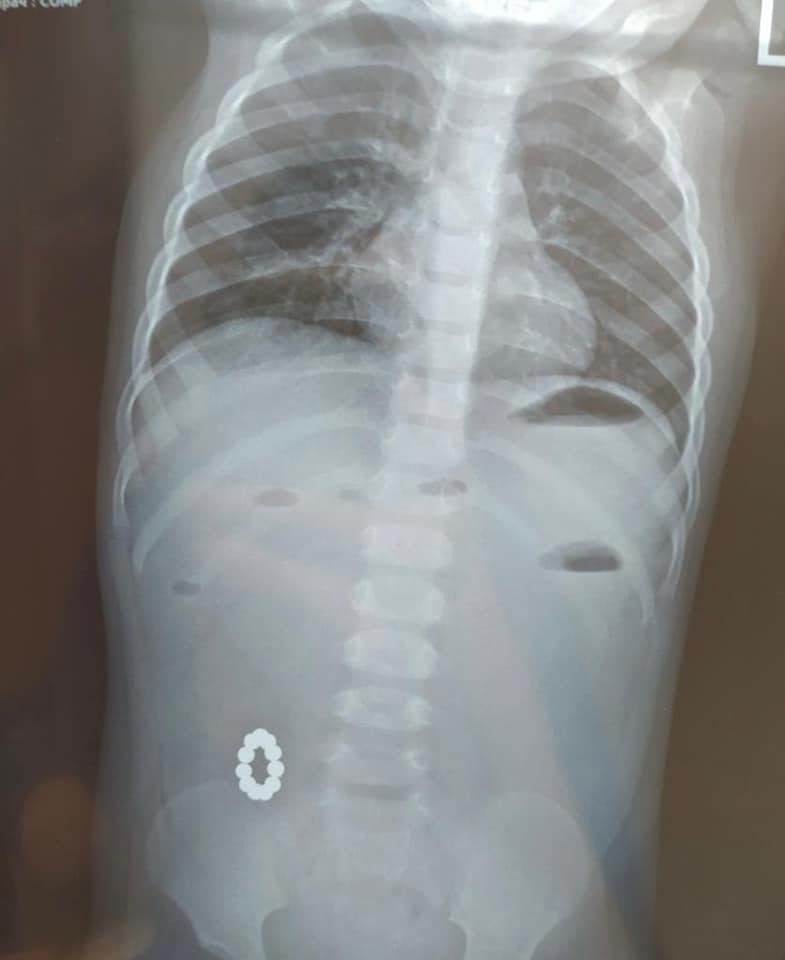

В Харькове годовалая девочка проглотила одиннадцать магнитов, ее пришлось оперировать. Об этом Vgorode сообщили в областной детской клинической больнице №1.

Ребенка привезли в больницу с подозрением на пищевое отравление. При обследовании оказалось, что в кишечнике находятся магниты, которые привели к непроходимости — тяжелой хирургической патологии.

"Мы уже не раз обращали внимание родителей на эти опасные игрушки особенно для малышей, — говорят в больнице. — Очередной медицинской бригадой в составе детских хирургов Ярослава Дегтярова, Игоря Черномаза, врача-интерна Оксаны Витренко, детского анестезиолога Евгения Виштала, операционной сестры Оксаны Арцыбашевой было успешно выполнено сложное оперативное вмешательство: удалены посторонние тела и ликвидирована непроходимость кишечного пути. Пусть девочка как можно скорее поправляется!".